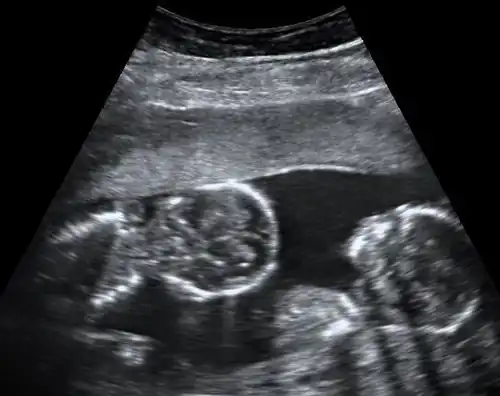

Abdominal ultrasonography of monoamniotic twins at a gestational age of 15 weeks. There is no sign of any membrane between the fetuses. A coronal plane is shown of the twin at left, and a sagittal plane of parts of the upper thorax and head is shown of the twin at right.

Monochorionic twins generally have two amniotic sacs (called Monochorionic-Diamniotic "MoDi"), but sometimes, in the case of monoamniotic twins (Monochorionic-Monoamniotic "MoMo"), they also share the same amniotic sac. Monoamniotic twins occur when the split takes place after the ninth day after fertilization.[2] Monoamniotic twins are always monozygotic (identical twins).[3] Monochorionic-Diamniotic twins are always monozygotic.